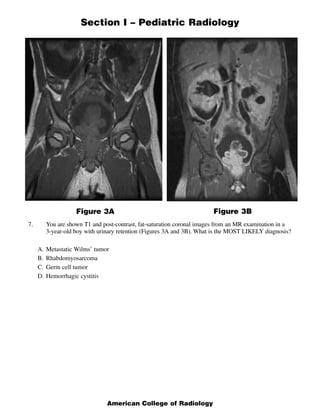

This document contains a multiple choice question and rationales from a pediatric radiology exam. The question shows MRI images of a 22-week fetus and asks for the most likely diagnosis. The rationales eliminate the other answer choices of posterior urethral valves, multicystic dysplastic kidneys, and bilateral ureteropelvic junction obstruction. The correct answer is Autosomal Recessive Polycystic Kidney Disease, as the images show enlarged, fluid-intensity kidneys without urine production, typical of this condition.